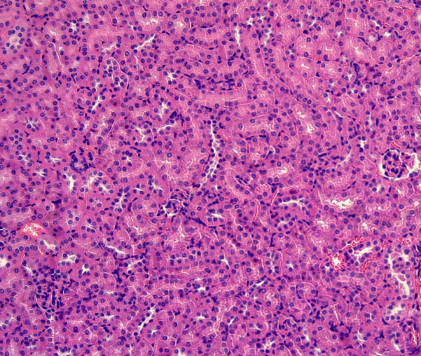

您当前的位置:  功能实验室 > 病理检测平台